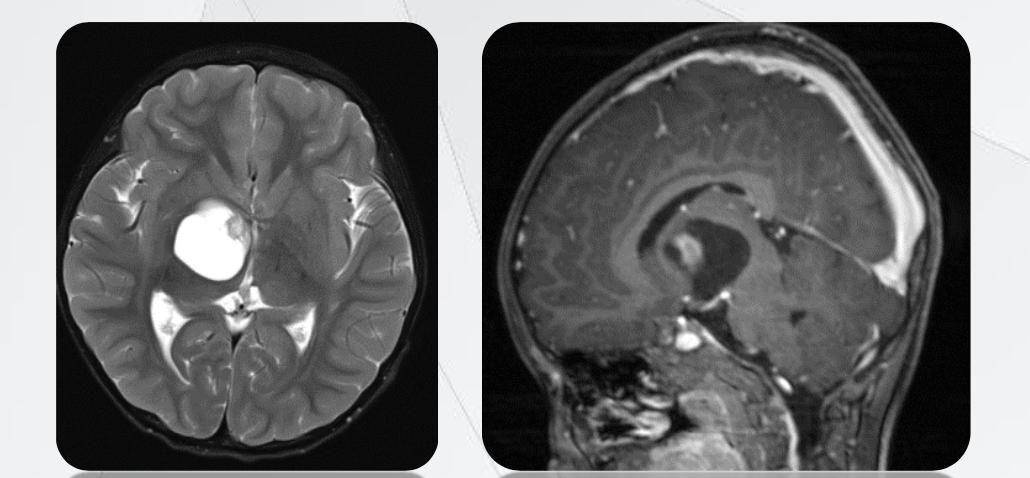

以中创五联的实际服务的“偏头痛”病案为例。临床时医生常以“少激动、多休息”为医嘱并辅以内科治疗,而中创五联通过分析患者头部CTA与MRI图像,进行多维滤波优化、多模态深度配准与融合重建,通过精准的三维模型,展现了患者偏头痛的病因是由于小脑动脉(基于CTA重建)挤压邻近三叉神经(基于MRI重建)所致,医生通过观察模型,获得了准确、可视的诊断与术前评估信息,使用微创手术帮助患者结束了持续了两年多的偏头痛,使患者生活质量显著提高。